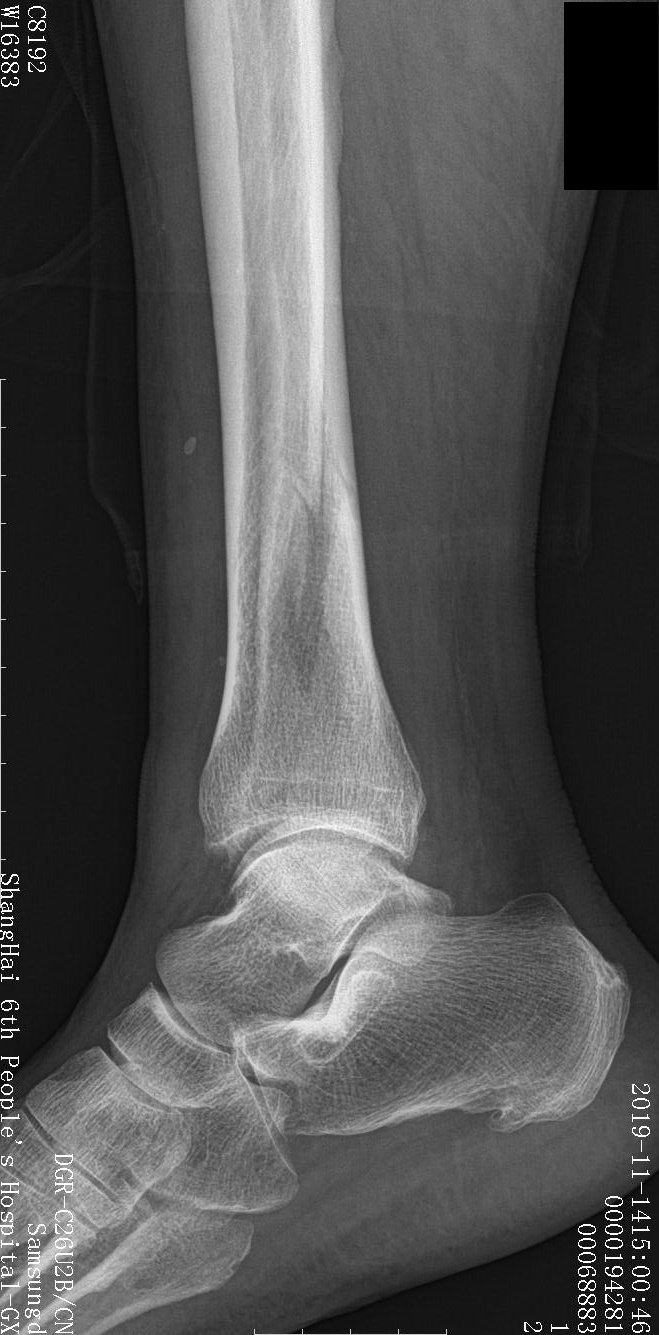

腓骨骨折需要做手術嗎 做與不做恢復時間分別多久 各有什麼隱患 做的話是怎樣一個過程 31歲? 1226 補充,醫生說脛腓骨骨折但沒明顯移位 脛骨裂痕不大可以不用手術 腓骨骨折處距離比較遠 不做手術可能要四個月才能下地 目前快消腫了 不動到基本不疼ます。腓骨を整復するには、骨折片の先端で骨膜を 2 mm むき ます。整復されたら、骨折片を一時的に固定します。長さと位置 を維持し骨折部位全体を圧迫するために、ラグ ネジを配置しま す。 注意:ラグ ネジまたはネジは、プレート配置を妨げたり腓骨腱 腓骨遠位骨折(手術後~退院までの2週間) 第3弾目の日記 中々タイムリーに書けないけども・・PCにじっと向かうのが足がしびれるので 気乗りがしない しかし、どんどん記憶が薄れるので・・ &知らなかった入院の仕組みやリハビリなど調べたことも

腓骨骨折需要手术吗 胫腓骨骨折